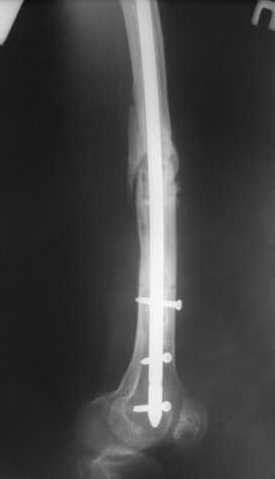

В приложении как раз видна эволюция использововшихся у нас большеберцовых гвоздей. Первый - дизайн как у UTN, второй - разнесены 45 градусные отверстия (зачем их вообще изначально так нелепо на одном уровне сделалм???), третий - убрано сиавшее лишним статическое отверстие, Herzog's bend перемещен более проксимально.

Забавненько смотрится... "век живи, век учись", как говорится. А чья мысль использовать блокируемые штифты для б/берцовой кости при переломах бедра? Такое встречалось где-то в литературе или это ваше ноу-хау?